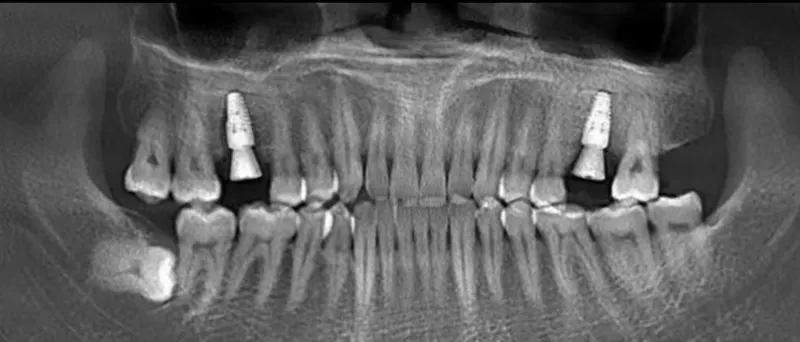

黃小姐在大醫院從事醫療工作為知名醫療人員,有時需上節目,發現前牙區不好看,牙齦發黑、牙齒不美,急於求助於牙醫師希望改善牙齒狀況,以避免損及醫療專業形象。